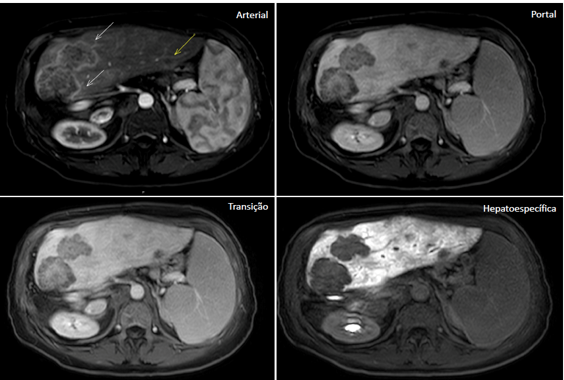

<content:encoded><![CDATA[<p>Rutinariamente, en la resonancia magnética (RM) del abdomen, se utiliza el contraste extracelular inespecífico (gadolinio), que se distribuye de acuerdo con la distribución de los vasos y capilares sanguíneos y determina, así, un patrón dinámico de impregnación de la lesión focal hepática en las fases arterial, portal (venosa) y equilibrio.</p>

<p>En casos seleccionados, se pueden indicar los contrastes intracelulares específicos, también denominados de hepato-específicos y que pueden ser de dos clases principales: (1) óxido de hierro superparamagnético y (2) hepatobiliares, siendo este último captado específicamente por las células hepáticas y con excreción renal (50%) y biliar (50%). En Brasil, está aprobado el contraste hepatobiliar, conocido como ácido gadoxético (Gd-EOB-DTPA, PrimovistÒ).</p>

<p>De esta manera, además de proporcionar los datos habituales del estudio dinámico, existe la etapa final de evaluación hepatobiliar, después de aproximadamente 10 a 20 minutos de la inyección endovenosa, en la cual el contraste entra en los hepatocitos a través de los transportadores de membrana (OATP1, B1/B3) y sale a través de proteínas dependientes de ATP resistentes a múltiples fármacos (MRP2, MRP3, MRP4), siendo el transportador MRP2 el encargado de excretar el contraste en el canalículo biliar.</p>

<h2 class="wp-block-heading"><strong>¿Cuáles son las indicaciones del contraste hepatobiliar?</strong></h2>

<p>Sabiendo que el ácido gadoxético es captado por los hepatocitos y excretado en aproximadamente un 50% por la vía biliar, se espera que un tejido hepático normofuncionante sea impregnado por el contraste en la fase hepatobiliar. De esta manera, la no captación del ácido gadoxético en la fase hepatobiliar infiere que no hay hepatocitos o canalículos biliares viables en la lesión evaluada.</p>

<p>Podemos enumerar 3 indicaciones principales en el uso del ácido gadoxético en la evaluación de lesiones focales hepáticas:</p>

<h3 class="wp-block-heading">1. <strong>Diferenciación entre hiperplasia nodular focal (HNF) y adenoma</strong></h3>

<p>El adenoma y la HNF son el tercer y segundo tumores hepáticos benignos más frecuentes, respectivamente.</p>

<p>El adenoma se caracteriza por cordones de hepatocitos y ausencia de conductos biliares o tractos portales, por lo tanto, no presenta captación en la fase hepatobiliar.</p>